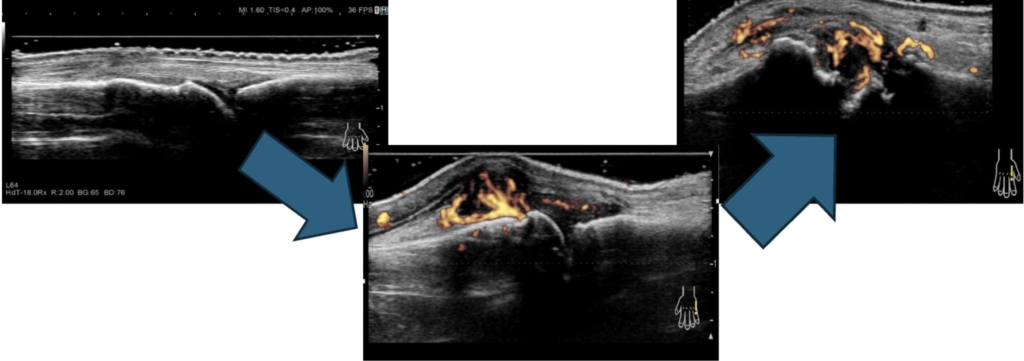

関節リウマチは、関節滑膜が炎症を起こすと厚みを持ち(滑膜肥厚)、滑膜内には異常な血流として示されます(滑膜炎)。これらを「関節エコーガイドライン」に沿って評価し治療に反映しています。

超音波検査は視覚的に炎症が確認でき患者様にもリアルタイムで画像を見てもらうことができるため関節リウマチの状態や治療効果を医師と一緒に共有することが出来ます。また、レントゲン画像では分からない小さな骨破壊(骨びらん)の確認も有用です。

現在の関節リウマチ治療は、早期発見・早期治療をすることで病気を抑えることができます。そのためにも適切な検査・投薬が必要不可欠です。